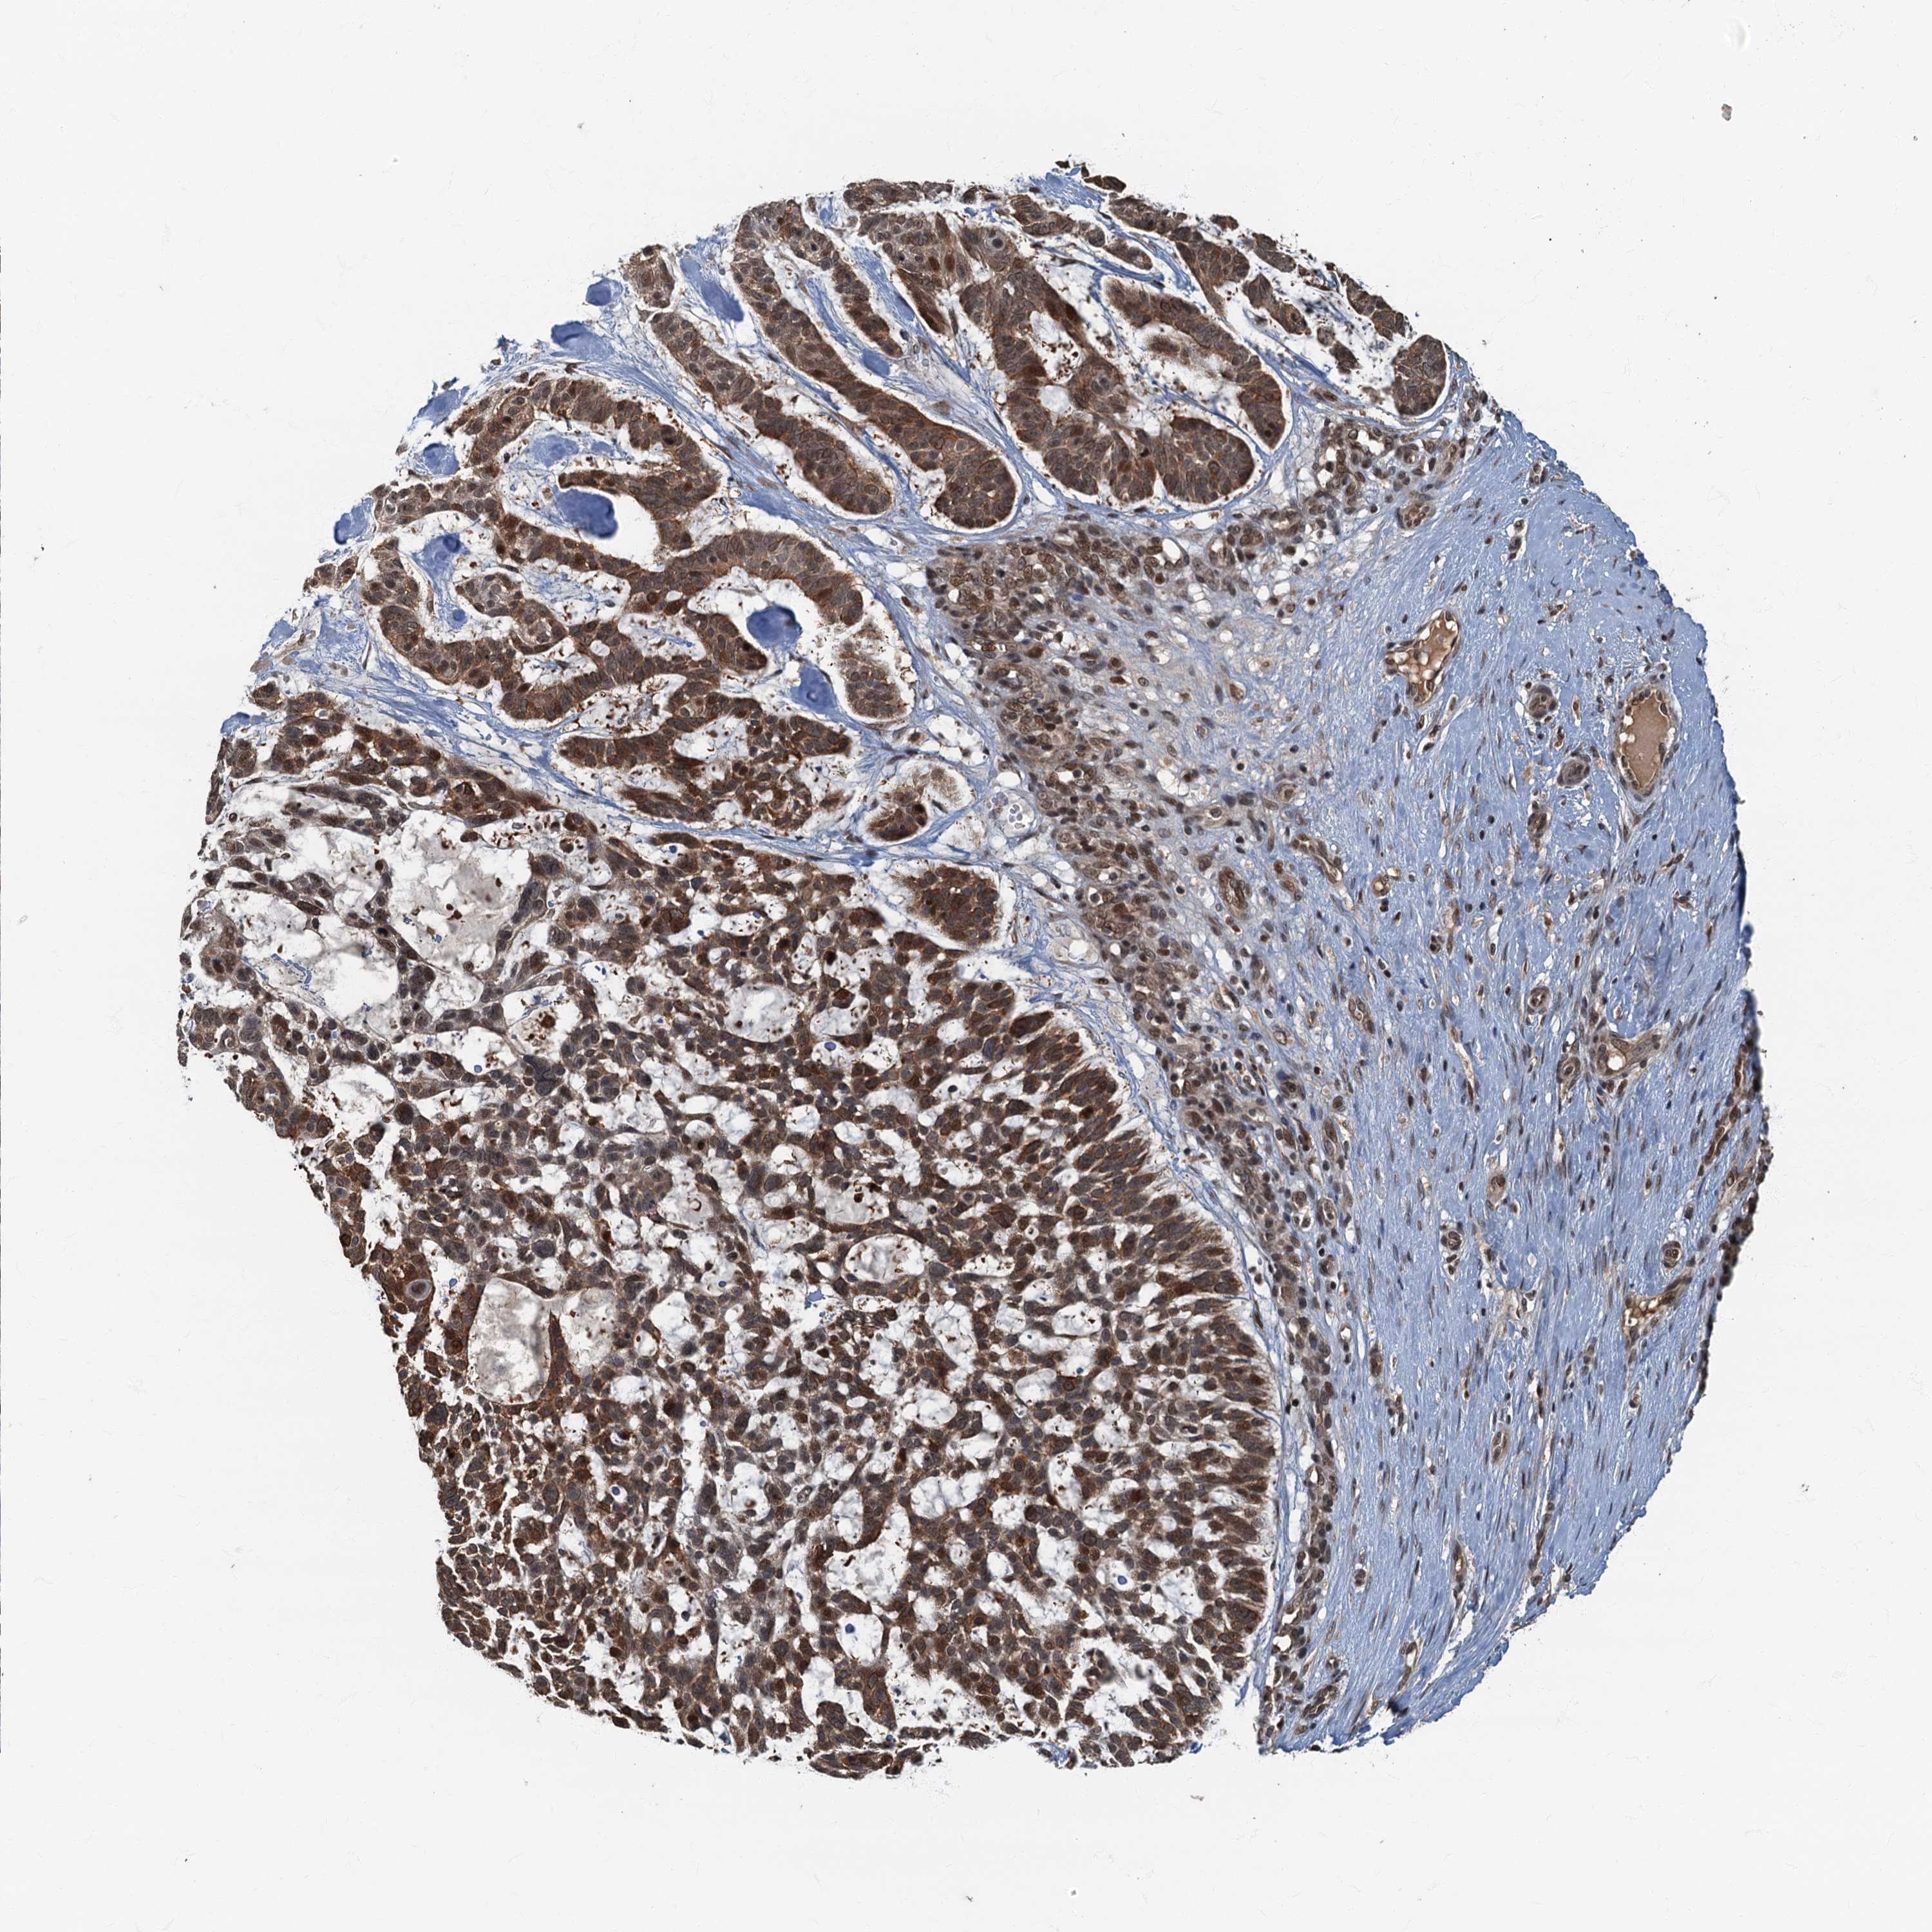

SKIN CANCER - Protein expressioni

A mouse-over function shows sample information and annotation data. Click on an image to view it in a full screen mode. Samples can be filtered based on level of antibody staining by selecting one or several of the following categories: high, medium, low and not detected. The assay and annotation is described here.

Antibody stainingi

Antibody staining in the annotated cell types in the current human tissue is reported as not detected, low, medium, or high, based on conventional immunohistochemistry profiling in selected tissues. This score is based on the combination of the staining intensity and fraction of stained cells.

Each image is clickable and will lead to virtual microscopy that enables deeper exploration of all samples and also displays staining intensity scores, fraction scores and subcellular localization as well as patient and tissue information for each sample.

Antibody HPA039407

Antibody HPA040057

Staining

High

Medium

Low

Not detected

Intensity

Strong

Moderate

Weak

Negative

Quantity

>75%

75%-25%

<25%

None

Location

Nuclear

Cytoplasmic/membranous

Cytoplasmic/membranous,nuclear

Squamous cell carcinoma, metastatic, NOS

Squamous cell carcinoma, NOS